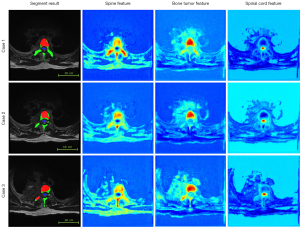

In order to observe the multi-target feature recognition, we added a feature visualization output module before the final classification softmax output layer of the network. This module transforms the features of different classification targets into grayscale [0–255] and then applies a color map to generate a heatmap. Figure 6 displays the feature heatmap distributions for different segmentation targets: the first column shows the segment result, the second column shows the spine, the third column shows the tumor, and the fourth column shows the spinal cord. In these heatmaps, the areas with darker red colors represent stronger or more prominent features, while the yellow regions indicate features with moderate intensity.